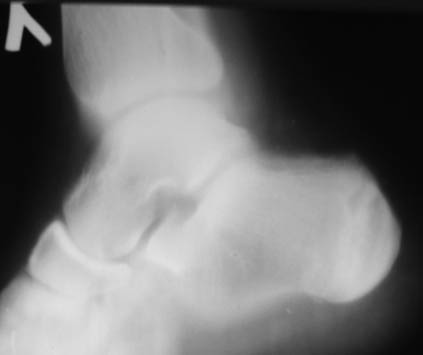

Уважаемый Николай Александрович Корышков, спасибо за проявленное

внимание к  случаю. Выкладываю снимки и томограммы левой пятки и

контрлатеральную, здоровую. Пациенту 19 лет, беспокоят ноющие боли.

Лечили блокадами и физиопроцедурами.